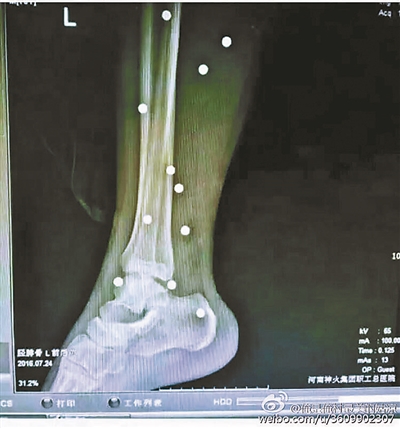

傷者體內取出的鋼珠

爆炸導致鋼珠遍布傷者身體各處

黃明的伯伯對北青報記者表示,由于黃明直接踩到了爆炸物,所以傷情最為嚴重,“他的腿被炸斷,身體內被炸進了40多顆鋼珠。手術后已經從體內取出29顆鋼珠,還有十多顆鋼珠沒有取出來?!备鶕S明的入院記錄,他全身有多處爆炸傷,且全身多處異物存留。

爆炸發生時,陳浩的位置與黃明靠得很近,因此也受傷較重。他告訴北青報記者,經過10多個小時的手術后,醫生從他身體里取出了12顆鋼珠。目前,他和黃明兩人經過手術后,已從重癥監護室轉至普通病房。其余三人中,陳剛的臀部受傷,當天晚上在醫院清理完傷口后便回了家,而同行的兩名女生身上有一些擦傷。